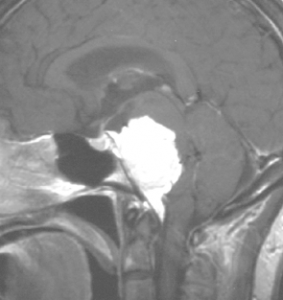

典型的な髄膜腫

この髄膜腫は中程度の大きさのものです。円蓋部髄膜種という最も多い最も手術の簡単なタイプです。麻痺や失語症やてんかんなどの症状はありません。とても美しくて若い女性の髄膜腫でしたが,子供に遺伝はしませんし,癌などと違ってタバコなどこれといった原因がなくて発生するものです。

最も見やすいのが,ガドリニウム造影剤を注射して撮影するものです。一般的に髄膜腫は造影剤で白く映し出されます。この腫瘍は左脳側にあります。MRIの軸面という輪切りの写真では左右が逆になりますから注意してください。脳を下から見た図になっています。MRIはいろいろな方向から腫瘍を見ることができますが,右は冠状断という正面から見た図です。よく見ると腫瘍の上と下のはじっこに線状に糸を引いたように造影される部分があります。これをテールサイン(しっぽのサイン)といいます。腫瘍が硬膜に沿って延びている可能性があることを示しています。